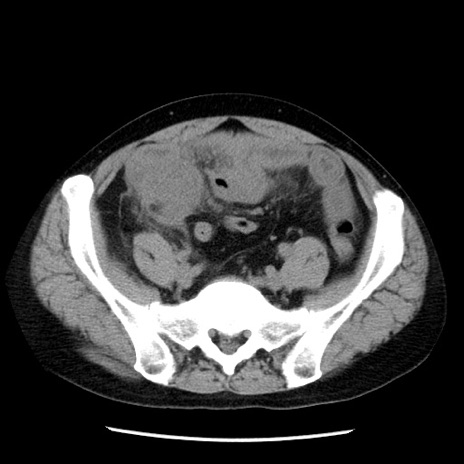

症例29(横断像)

【症例】40歳代男性

【現病歴】2日前から胃痛あり。徐々に周期的な激痛に変化した。本日になっても激痛があるため受診。

【身体所見】意識清明、BT 38-39℃台あり、腹部:膨満、やや硬、右下腹部に圧痛あり。

【データ】WBC 8500、CRP 23.26